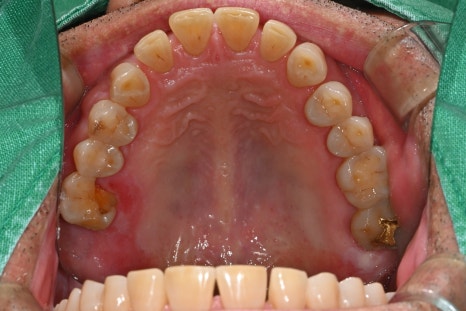

초진 내원 당시

60대 남성분으로, 오른쪽 위 어금니가

갑자기 깨지면서 씹을 때 통증이 심해졌고,

주변 잇몸까지 붓는 증상이 함께 있었습니다.